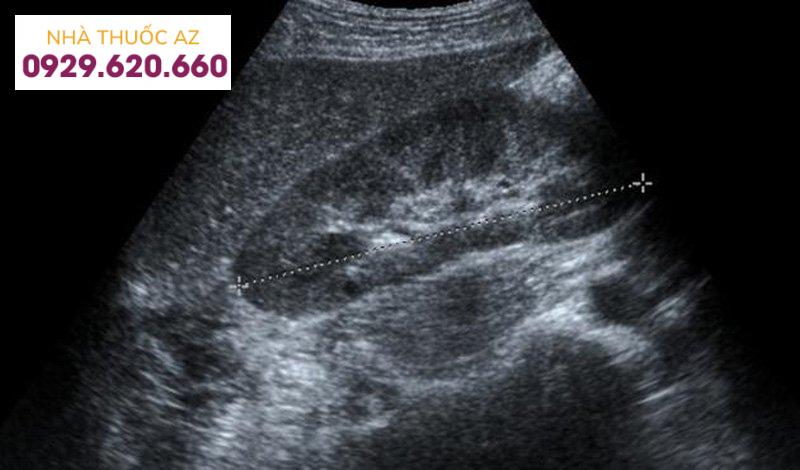

3.2 Hình ảnh của gan nhiễm mỡ trên siêu âm

Bệnh gan nhiễm mỡ được phát hiện trên siêu âm chủ yếu dựa vào các triệu chứng như tăng độ sáng tại các vùng khác nhau của gan hoặc tăng độ sáng của mô gan khiến cho đường bờ của các cấu trúc mạch máu bị mờ đi.

Trên hình ảnh siêu âm, hình thái gan sẽ xuất hiện những đốm sáng rải rác hoặc tập trung thành từng khu. Tình trạng này sẽ có sự khác nhau tùy theo mức độ nhiễm mỡ gan ở từng người. Khi gan bị nhiễm mỡ, bác sĩ siêu âm sẽ không nhìn thấy hoặc thấy không rõ hệ thống mạch bên ngoài trên gan.

Bên cạnh đó, độ hồi âm của gan bình thường bằng hoặc tăng nhẹ so với vỏ thận hoặc lách. Khi gan bị nhiễm mỡ, hồi âm của gan sẽ vượt trội so với vỏ thận và lách, đồng thời có sự suy giảm của sóng siêu âm, mất sự rõ nét của cơ hoành và phân định nghèo nàn các cấu trúc trong gan.

3.3 Đánh giá mức độ gan nhiễm mỡ trên siêu âm gan nhiễm mỡ

Bác sĩ có thể đánh giá mức độ gan nhiễm mỡ dựa vào hiện tượng tăng độ sáng của nhu mô gan trên hình ảnh siêu âm gan như sau:

Mức độ 1: gan tăng âm nhẹ, mức độ hút âm chưa có sự thay đổi đáng kể, vẫn còn xác định được cơ hoành và đường bờ các tĩnh mạch trong gan.Mức độ 2: gia tăng sự lan tỏa độ hồi âm và hút âm, khả năng xác định được bờ các tĩnh mạch trong gan và cơ hoành đã giảm đi nhiều.Mức độ 3: gia tăng rõ rệt mức độ hồi âm và hút âm, không còn nhận diện được đường bờ các tĩnh mạch trong gan, cơ hoành, một phần nhu mô gan ở phân thùy sau gan phải trên mặt cắt dưới sườn.